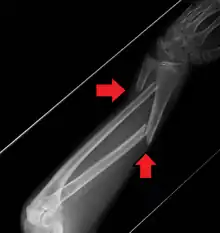

Midshaft fracture of the radius and ulna

A fracture of the forearm can be classified as to whether it involves only the ulna (ulnar fracture), only the radius (radius fracture), or both radioulnar fracture.